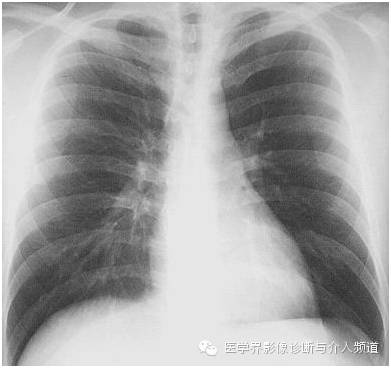

很多时候只给一张胸片,你能看出上图异常吗?

对比一张正常胸片:

看出异常所在了吗?

没关系,继续:

异常:双肺门淋巴结肿大。